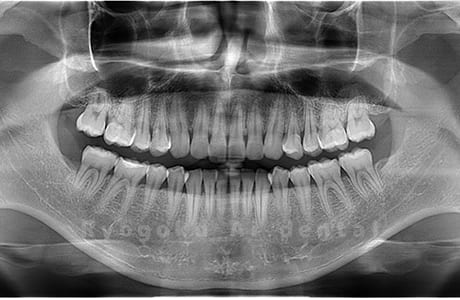

Case02

- 原因

- 下顎の水平埋伏智歯

- 治療内容

- 下顎の水平埋伏智歯を抜歯

<リスク・副作用>

手術後は痛み、腫れ、痺れなどの副作用が生じる場合があります。